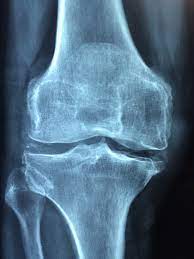

관절염 치료법

① 보존적인 치료법

- 항염증 약물, 운동 요법 등으로 진행

- 초기 퇴행성 관절염 환자에게 적합

- 근력 및 근육량 키워서 유지

- 통증 줄이고, 일상적인 활동 가능하도록 개선

② 수술적 치료법

- 관절 연골이 많이 닳고 손상이 심한 환자에게 적용

- 인공관절 수술, 교정 절골술, 관절 내시경 등이 있음

- 보존적 치료에도 불구하고 통증‧기능장애가 계속 악화하면 고려

- 불필요한 관절경 치료는 효과 거의 없고, 부작용 위험 증가

③약물 치료

- 진통 억제 및 항염증제재를 사용하여 관절염으로 인한 통증을 없애고 관절 기능 유지하기 위함

- 이 약들이 퇴행성 관절염을 완치시킬 수 없으나 통증 경감에 효과가 있고, 이로 인해 일상생활이 가능

- 심한 통증이 있는 경우 흔히 ‘뼈주사'라고 불리는 스테로이드 제재를 관절 내에 주입하는 경우가 있으며, 증상의 호전에는 효과가 있음

- 장기적으로 보면 연골의 변성을 촉진시켜 해로운 영향을 끼친다.